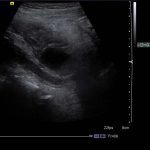

- Superficial to this is a 2 x 2.5 cm ovoid hypoechoic structure which appears separate from the adjacent bowel and shows no internal vascularity

Superficial to this is a 2 x 2.5 cm ovoid hypoechoic structure which appears separate from the adjacent bowel and shows no internal vascularity, concerning for a periappendiceal abscess.